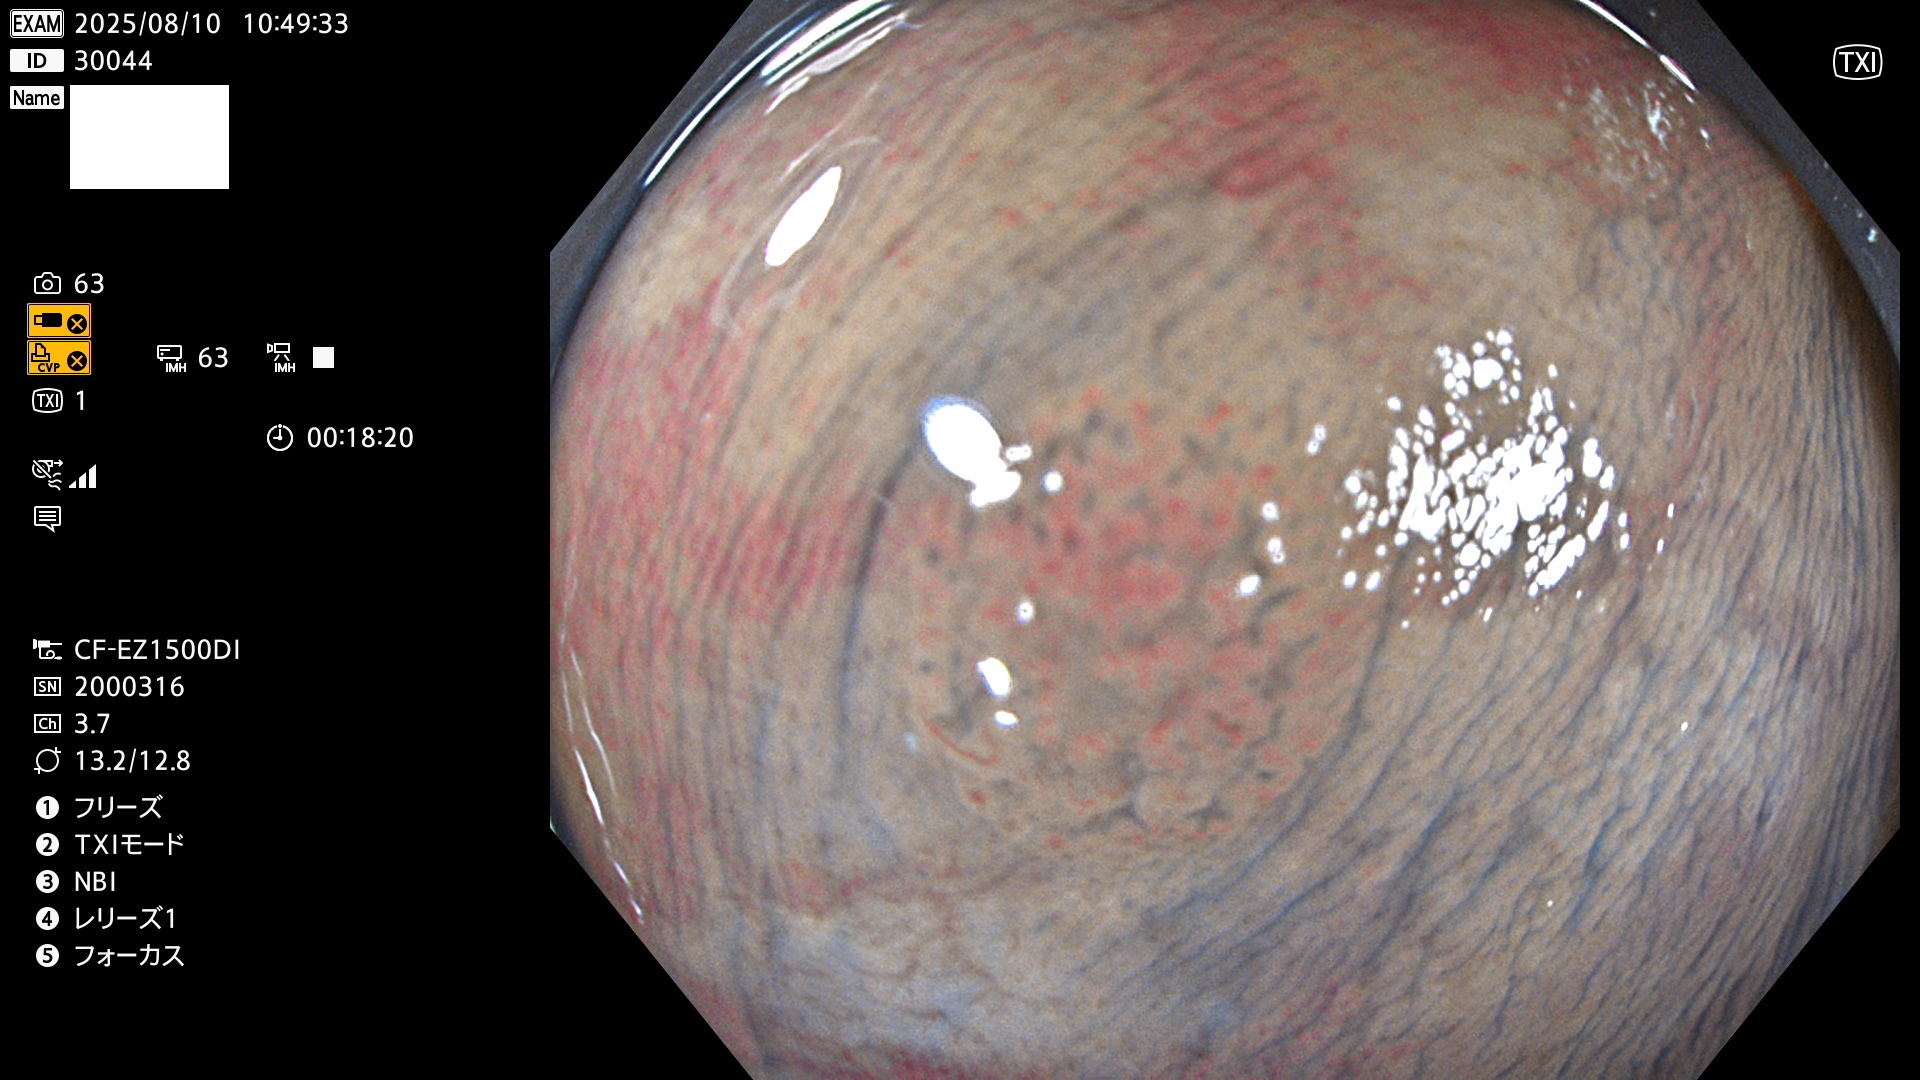

完全に平坦な物をUb、陥凹している物をUcと呼びます。Ubは認識が困難で、Ucはびらん(炎症)と紛らわしいために見落とされやすく、「内視鏡後・大腸癌」の原因になります。

毎週の検査(木・金・土・日)に発見されたUbとUc型・腺腫を、その週の日曜の夜にUPし1週間、提示します。

2025年8月7日〜8月10日の4日間(35件)6個 (Uc_ADR=6個/35人=17%)